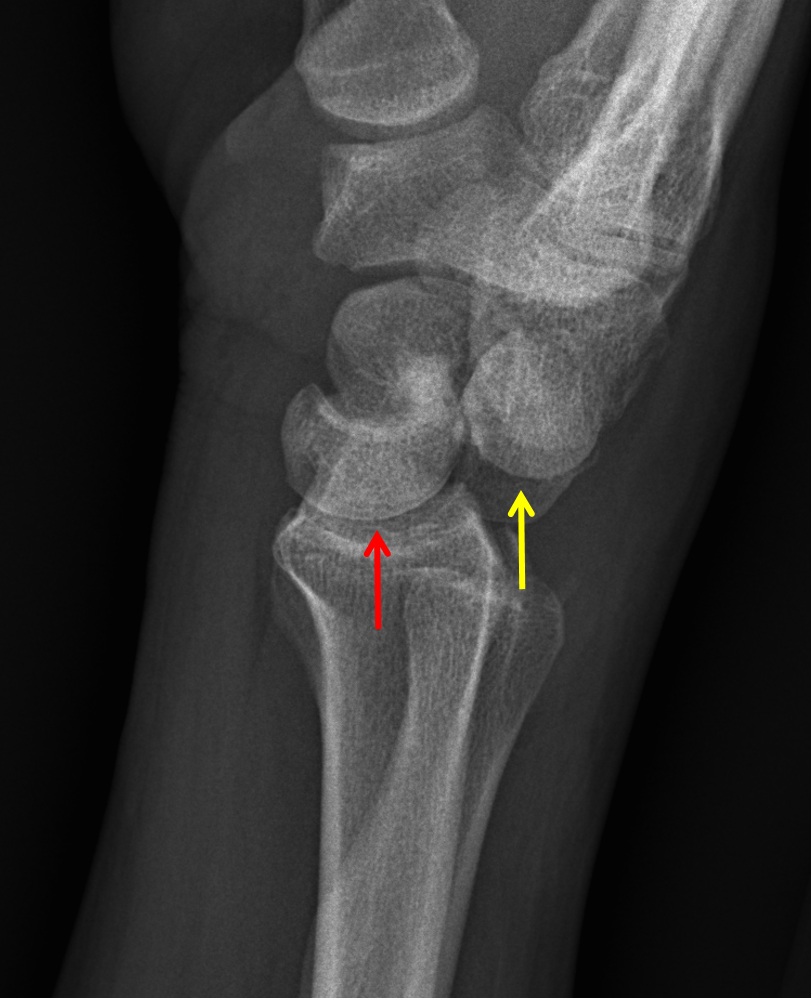

CaseStacks.com - MSK Radiograph Case #28

CaseStacks.com - MSK Radiograph Case #28 www.casestacks.com

dislocation perilunate casestacks lunate msk